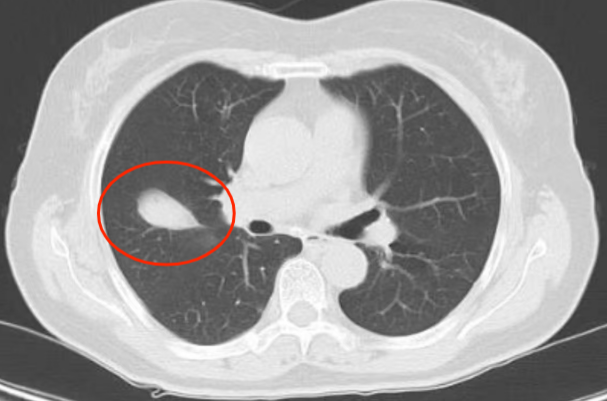

近年来,贵州航天医院各科室紧跟医学前沿,不断强技术、补短板,大力开展新技术、新项目,完成了许多高精尖、高难度、本地区“首例”的技术,填补了医院医疗技术空白,满足了群众日益增长的医疗需求。 贵州航天医院呼吸与危重症医学科是贵州省内呼吸疾病治疗规模最大,诊疗项目最全的呼吸疾病品牌科室,呼吸介入技术达到了全国先进水平,在贵州省内处于领先的地位。 本期,我们将为大家带来呼吸与危重症医学科特色技术——氩氦刀冷冻消融技术治疗肺癌、高危肺结节。 案例分享 患者在体检时发现右肺结节(10mm),就诊于当地我院一专科联盟合作医院,但因当地医疗条件有限,患者通过专科联盟绿色通道前往我院就诊,入院后,通过经皮肺穿刺活检,病理诊断为右肺原位腺癌,科室立即组织专家开展肺结节多学科会诊(MDT),为患者制定诊疗方案。 经充分的沟通下,患者及家属拒绝手术切除。科室再次严格讨论评估,患者情况满足氩氦刀冷冻消融术指征,再次将治疗方案与患者及家属沟通同意后,为患者制定并成功实施氩氦刀冷冻消融术。 冷冻消融术中 术后,患者定期复查,恢复效果良好。 术前 术后即刻 术后1月(反应性增大) 术后6月(纤维条索) 术后12月(纤维条索变细) 什么是氩氦刀冷冻消融技术 氩氦刀冷冻消融技术是一种先进的微创超低温冷冻消融肿瘤的医疗技术,它利用氩气和氦气的快速温度变化特性,实现对病变组织的精准冷冻和复温,以达到消融和破坏肿瘤细胞的目的。 氩氦刀冷冻消融技术原理 氩氦刀冷冻消融技术基于焦耳-汤姆逊效应,通过氩气和氦气的快速交换实现局部组织的超低温冷冻(-140℃到-190℃)和快速复温(20℃到45℃),当氩气通过金属杆尖端的蒸发器时,其气压突然降低,会大量吸收周围的热量,使金属杆尖部的气温迅速下降到超低温;随后,氦气在极短的时间内使组织迅速复温,通过热胀冷缩的原理,使肿瘤细胞爆裂。 (一)直接杀伤( 靶区冷冻消融效应) 1.快速冷冻(降温段):细胞内冰晶快速生长并撕裂细胞,导致细胞损坏。 2.慢速冷冻(低温段):细胞外冰晶生长导致水渗出细胞,造成细胞脱水。 3.升温:水迅速进入细胞,导致细胞涨破。 (二)间接杀伤( 冷冻的血管栓塞效应) 病灶区域快速冷热交替,引起微血管细胞脱水、蛋白质变性、微血管损伤、 冰晶及微血栓在微血管内形成,导致血小板聚集、血管栓塞, 局部细胞缺血坏死。 (三)抗肿瘤免疫( 冷冻免疫激活效应) 随着肿瘤细胞的破裂和坏死,促使肿瘤免疫调节因子停止分泌,逆转免疫抑制状态;可调控表面抗原,促进淋巴细胞增殖,提高身体抗肿瘤免疫能力。 氩氦刀冷冻消融技术优势 (一)精准度高:通过精确的靶点定位和温控技术,可实现对病变组织的精准冷冻和复温,避免损伤正常组织。 (二)微创治疗:对周围正常组织的热损伤小,无需开胸开腹,仅有一个针孔,恢复快,几乎无疤痕。 (三)适应症广:肺腺体前驱病变(癌前病变)、甲状腺结节、乳腺结节等;多原发磨玻璃肺结节,因各种原因不适合手术的早期肺癌、肝癌等;内科治疗无法控制的少发转移瘤等。 (四)可重复治疗:由于冷冻治疗对身体的创伤和痛苦较小,可以多次重复进行治疗,这对巨大的肿瘤和多发的肿瘤尤其适用。 (五)无毒性:冷冻治疗是以物理方法杀灭肿瘤,不向体内注射任何药物,避免外科手术、化放疗等对身体带来的巨大创伤和毒副作用,能有效减轻患者肿瘤负荷和痛苦,因此与化放疗、分子靶向药物等治疗方式相比属于无毒治疗。 氩氦刀冷冻消融技术对于早期肺癌、高危结节,可作为手术的替代治疗。对于晚期较大的肿瘤可作为姑息治疗,增强综合治疗的效果,可减少肿瘤负荷,减轻症状,提高生活质量,延长生存时间。 近年来,随着医学影像技术发展和肺癌筛查的广泛开展,肺内结节的检出率显著提高。无论肺内磨玻璃结节还是实性结节,单发或多发,都需要引起重视,定期复查,动态观察结节变化,如有需要请积极治疗。 贵州航天医院 呼吸与危重症医学科专家团队 廖江荣 国务院政府特殊津贴专家、遵义市呼吸疾病临床医学中心学科带头人、二级教授、主任医师 学术任职: 亚洲冷冻治疗学会副主席 第二届中国医药教育协会介入微创专业委员会呼吸分会副主任委员 中国抗癌协会肿瘤微创治疗专业委员会常务委员 中国防痨协会结核病转化医学专业分会常务委员 第一届中国人体健康科技促进会呼吸介入专委会常务委员 中国医疗保健国际交流促进会结核病学分会第三届委员会常务委员 中国抗癌协会肿瘤微创治疗专业委员会粒子治疗学组第四届委员会委员 中国结核病防治综合质量控制专家指导委员会委员 “西部呼吸介入联盟”副理事长 专业擅长: 呼吸系统(肺)疑难病的诊断及危重病的抢救,呼吸系统(肺)感染性、疑难性疾病介入快速诊断(ROSE),尤其在肺癌、肺小结节早期诊断,肺癌微创综合靶向治疗,难治性、复治性、重症肺结核诊疗,硬质支气管下复杂性气道狭窄诊治,纤支镜介入治疗气道肿瘤、结核、气道狭窄(球囊扩张、支架植入、高频电刀、氩气刀、冷冻、灌洗、注药、微波消融),间质性肺疾病的诊疗上具有极高水平;带领团队勇于创新,在贵州省率先开展多项新技术、新疗法,如CT引导下及纤支镜下I125粒子植入及CT引导下微波、冷冻消融介入治疗肺癌等多项新技术,带动了贵州省肺部疾病的介入治疗水平提高。 唐永江 四川大学华西医院 呼吸与危重症医学科 副主任医师 呼吸危重症医疗组长 香港中文大学博士 美国康奈尔大学访问学者 贵州航天医院 呼吸与危重症医学科 学科带头人 主要从事呼吸危重症(特别是呼吸重症感染)的临床及科研工作。 PCCM专培结业医师 中华医学会呼吸病学分会呼吸危重症学组秘书 中华医学会呼吸病学分会ECMO工作组成员 四川省医学会呼吸病学专委会介入学组委员兼秘书 发表文章20余篇,主持及参与多项国家自然科学基金及省卫健委基金。 蒋 婷 呼吸、感染党支部书记,呼吸与危重症医学科主任,副主任医师 专业擅长:从医20余年,在呼吸系统疾病、介入呼吸病学、肺部结核、肺部肿瘤等方面具有丰富的临床经验和专业技能,尤其是慢性阻塞性肺疾病、支气管扩张、肺结核、耐药肺结核、肺癌、胸腔积液等肺部疾病的诊治、微创介入、危重病患者抢救。 现任中国防痨协会人兽共患结核病专业分会委员,中国女医师协会第一届介入专业委员会委员,贵州省基层呼吸疾病防治联盟-间质性肺疾病联盟委员,贵州省防痨协会第七届理事会理事,贵州省中西医结合学会呼吸专业委员介入呼吸病学组委员,贵州省遵义市中医药学会中西医结合肺病(呼吸)分会副主任委员,贵州省遵义市中医药学会中医肿瘤专业委员会常委;发表论文数篇,参与并主持多项科研项目。 王 云 中共党员,呼吸与危重症医学科一病区副主任,副主任医师 专业擅长:擅长呼吸系统常见病及疑难危重症、介入呼吸病学、肺部肿瘤疾病的诊治,尤其擅长快速现场评价(ROSE)技术。 贵州省中西医结合学会呼吸专业委员会介入呼吸病学组委员,遵义市中医药学会中西医结合肺病(呼吸)分会委员,贵州省中西医结合学会第六届呼吸专业委员会委员。 李桂凤 中共党员,呼吸与危重症医学科三病区主任,副主任医师 专业擅长:从事呼吸系统疾病、结核病学、介入呼吸病学、肿瘤综合治疗、呼吸康复等临床工作20余年,擅长呼吸内科常见病、多发病及疑难重症危重病症的诊治,尤其对重症疑难结核及耐药结核病、介入治疗(肺)呼吸系统疾病、呼吸危重病抢救等方面具有较高诊疗水平。 中国防痨协会非结核病专业委员会委员,贵州省中西医结合学会第六届呼吸专业委员会委员,贵州省康复学会睡眠障碍康复专业委员会委员,遵义市呼吸内科医疗质量控制中心委员,遵义市落实民生实事结核病筛查阅片专家组成员;主持及参与实用新型专利3项。 周裕祥 中共党员,呼吸与危重症医学科四病区主任,副主任医师 专业擅长:经皮肺介入、经血管介入诊疗技术。 贵州省中西医结合学会呼吸专业委员会介入呼吸病学组常务委员,中国医师协会呼吸医师分会介入呼吸病学工作委员会呼吸病血管介入学组委员,贵州省中西医结合学会呼吸学分会委员,遵义市医学会放射肿瘤治疗学分会委员,中国医药教育协会介入微创呼吸分会委员,北京健康促进会中青年专家委员会胸部疾病精准活检分委会委员;曾赴重庆医科大学RICU、珠海市人民医院介入科进修学习。 杨 芳 中共党员,呼吸与危重症医学科内镜中心主任,副主任医师 专业擅长:从事临床工作约20年,对呼吸危重病的救治有独到的见解,尤其擅长呼吸系统疾病的介入诊疗,对呼吸内镜下的诊治及经皮肺穿刺诊疗技术具有丰富的临床经验。 亚洲冷冻治疗学会委员,中国医药教育协会介入微创呼吸分会委员,西南结核病医院联盟第二届委员会秘书/委员,贵州省中西医结合学会第六届呼吸科专业委员会委员,贵州省中西医结合学会呼吸专业委员会介入呼吸病学组秘书,贵州省中西医结合学会呼吸专业委员会基层康复学组副组长,贵州水利电力医学科学技术会高原医学分会委员,遵义市中医院学会中西医结合肺病(呼吸)分会秘书/常务委员,遵义市医学会肿瘤学分会(第二届)委员,遵义市医学会放射肿瘤治疗学分会第二届委员;主持及参与科研课题多项,参编著作《呼吸内镜操作技术规范》、《介入结核病学》,发表论文数篇。 贵州航天医院 呼吸与危重症医学科简介 贵州航天医院呼吸与危重症医学科以呼吸危重症和介入呼吸病学为强力推手,以肺部感染性疾病及肺癌、肺小结节的早期精准诊疗、慢性呼吸疾病康复治疗为特色,以人才团队建设为核心的科室发展模式,现已成为贵州省内呼吸疾病治疗规模最大、诊疗项目最全的呼吸疾病品牌科室。是贵州省医学重点学科、临床医学重点专科建设单位,遵义市首批呼吸重点学科、重点专科建设单位。是国家卫健委能力建设和继续教育肿瘤微创介入建设中心、贵州省县级医院微创介入培训中心、遵义市呼吸疾病临床医学中心。是国家呼吸医疗质量控制与管理哨点医院、遵义市呼吸内科专业医疗质量控制中心。是中国医药教育协会介入微创呼吸分会呼吸介入技术培训中心单位;国家卫健委海医会呼吸分会ROSE专委会“诊断性介入肺脏病学快速现场评价”培训基地;中国肺癌防治联盟“贵州航天医院肺结节诊治”分中心,中国人体健康科技促进会呼吸介入技术培训基地,贵州省中西医结合会呼吸学分会呼吸介入专委会主委单位。 基本情况 平均每年开展气管镜诊疗约4000例,经皮肺穿刺介入诊疗近千例,开展的项目包括经支气管镜(软、硬)下冷冻、氩气刀、高频电刀、球囊扩张、支架置入、超声内镜诊疗等气道介入诊疗技术,经皮肺穿刺活检及肿瘤消融术(微波、冷冻)、ROSE技术、内科胸腔镜诊疗及经血管介入诊疗技术,且多项呼吸介入诊疗技术在省内处于领先水平。 诊疗范围 专科擅长:致力于呼吸系统感染性、疑难性疾病的介入快速精准诊疗;肺癌与肺小结节早期精准诊疗水平项目提升。擅长呼吸系统(肺)疑难病的诊断及危重病的救治,尤其是肺癌、肺小结节的早期诊断,肺癌综合靶向治疗,肺结核综合诊疗等肺部疾病的介入诊疗在贵州省内处于前沿水平。 肺结节MDT门诊 贵州航天医院呼吸与危重症医学科微创介入诊疗技术已达到国内前列,省内领先水平,是亚洲冷冻治疗学会常务理事单位,并获批成立遵义市肺结节多学科(MDT)微创诊疗中心。 出诊信息 出诊时间: 周一至周五 8:00--12:00;14:00--17:00 出诊地点: 遵义市肺结节多学科微创诊疗中心(MDT)门诊(贵州航天医院呼吸综合楼1楼) 呼吸与危重症医学科与心胸外科、医学影像科、麻醉科等科室建立了多学科(MDT)会诊机制,结合患者情况,通过采取外科手术、冷、热消融等多种治疗手段,帮助患者安全、有效、精准、科学、快速治疗肺结节,单次消融手术时间约半小时左右,几乎没有疼痛,且并发症少,3-5天即可出院,有效减少了患者因开刀手术需长时间恢复的痛苦。 一审一校:周裕祥、黄成成